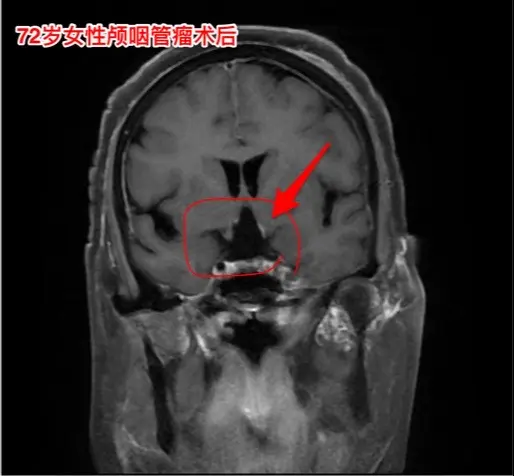

颅咽管瘤不单单是小孩子得的病!很多人认为颅咽管瘤是小孩子得的病,其实各个年龄段的人都可以患颅咽管瘤,我见过的颅咽管瘤病人年龄跨度从不到一岁到八十多岁! 相对而言,小孩子群体中(小于15岁)颅咽管瘤的发生率比较高! 这个72岁的山西晋城市老人在古稀之年患上了颅咽管瘤,病理报告是乳头型颅咽管瘤。10月25日在我科作了手术,11月13日出院。 老人在住院前胃肠功能不好,经常腹胀、消化不良。手术后也是经常感觉腹胀、食欲不振,身体康复过程相对比较缓慢。 老年人一般来说都伴有老年性疾病,比如糖尿病、高血压病、高脂血症、动脉硬化,身体大脏器机能下降,所以老年人患颅咽管瘤,作手术后恢复会比较慢,出意外的风险会增加,尤其是血管方面的并发症会增加,比如深静脉血栓、心肌梗死等。